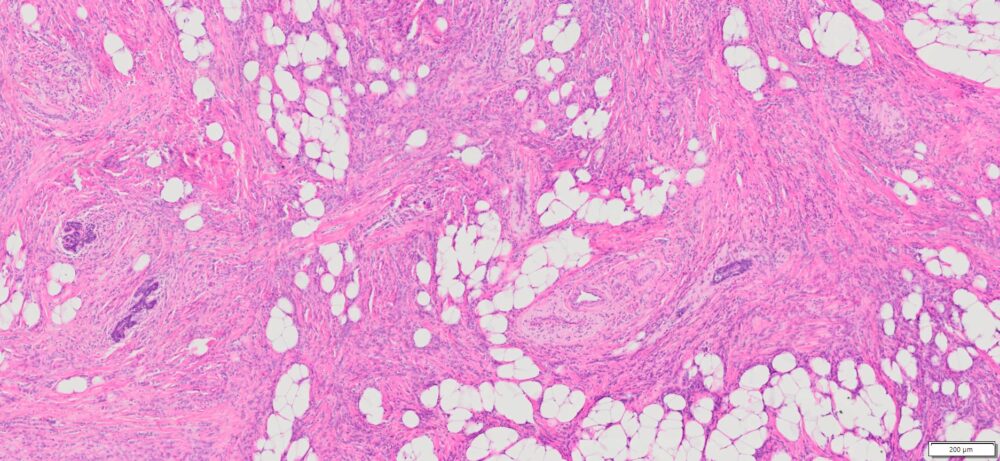

| HuPS-02033T1 | Breast | Invasive lobular carcinoma | No | Female/56 | 45% | II | pT3pN2aMx | NA |